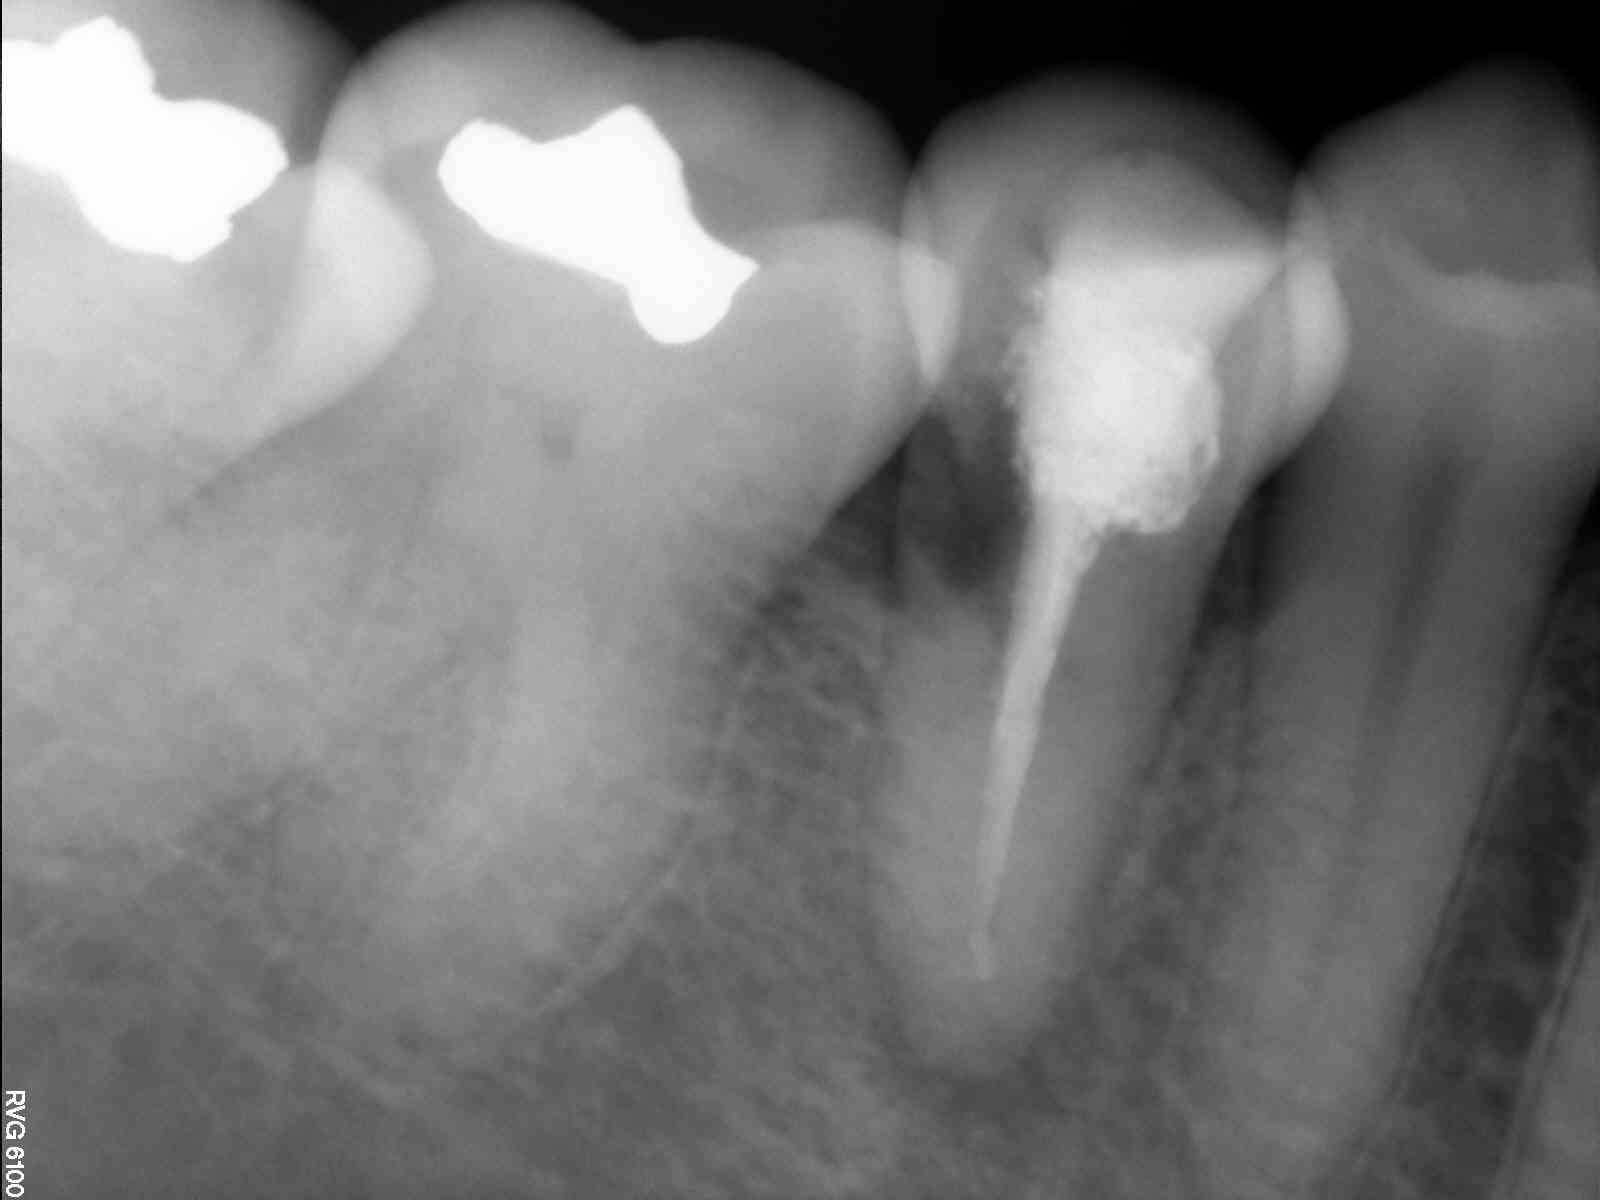

Fig. 2: Periapical radiograph of the initial situation.

A 38-year-old woman presented to the dental practice complaining of discomfort in the area of tooth #45. Her symptoms worsened with chewing. The patient’s clinical history was not contributory. She reported that root canal therapy had been performed on tooth #45 owing to caries and that she had undergone orthodontic treatment seven years earlier. The clinical tests found pain on percussion and a distal probing pocket depth of more than 3 mm.

The radiographic examination showed periapical radiolucency and a radiolucent lesion in the cervical area of the tooth (Figs. 1 & 2). To determine the extent and depth of the lesion, a CBCT scan was performed (Fig. 3). Based on the CBCT images and 3D reconstructions, a diagnosis of Heithersay Class III external cervical invasive root resorption (ECIR) was determined in an endodontically treated tooth with symptomatic periapical periodontitis. The patient was informed of the diagnosis, treatment plan alternatives and prognosis of the case.